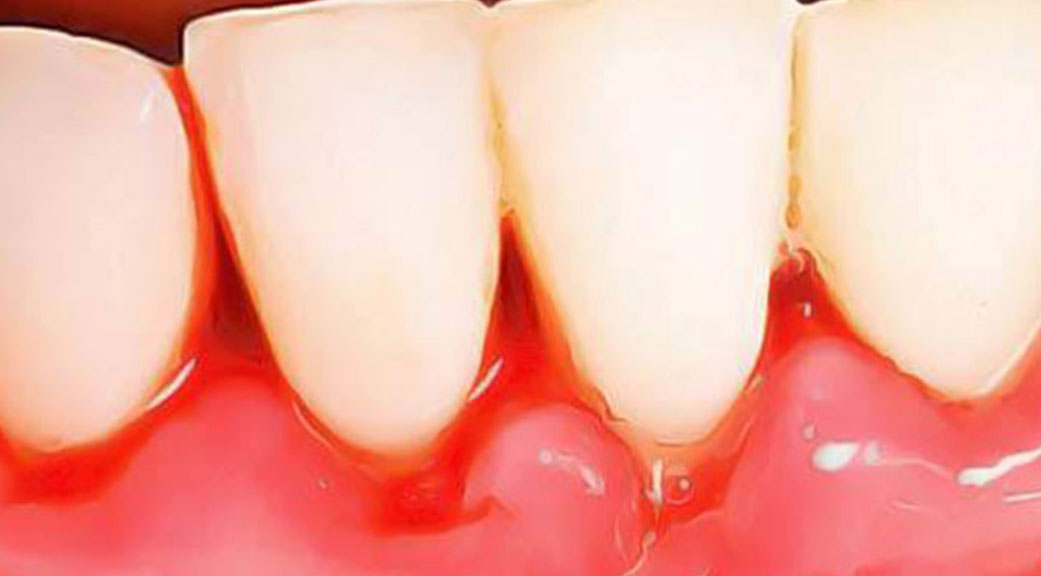

Maladies gingivales